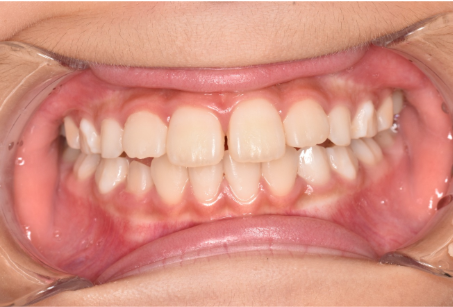

治療後

| 術後の経過・現在の様子 | マイオブレース使用時間を守っていただき、口腔機能トレーニングに真面目に取り組んでいただいたので、歯並びがきれいに整いました。 ご本人含め、ご家族には「きれいになってきた!」と、ビフォーアフターの結果にとても喜んでいただいております。 現在は後戻りが起きないよう、保定装置(リテーナー)を使っているほか、定期的に来院いただき治療状況を確認しています。 |